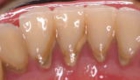

重度歯周炎

歯周ポケットが6mm以上で、歯槽骨の破壊がかなり進んだ状態。

重度歯周炎では、プラークや歯石が多量に沈着し、歯槽骨が大きく溶かされています。歯ぐきから出血、排膿を伴い、口臭がします。歯は歯槽骨の支えを失い、大きく動揺します。物を噛むと力を支えきれず、痛みがでたり、力が入らず噛めないといった症状が起こります。

さらに進行すると、歯が自然に抜けてしまいます。

重度歯周炎の症例です。歯石が多量に付着しており、歯ぐきが下がり、歯がくらぐらしています。

歯が支えを失って前に移動し、歯と歯の間に隙間ができています。

細菌が顎の骨の奥深くまで侵入し、歯槽骨がほぼ歯根の先端まで破壊されています。